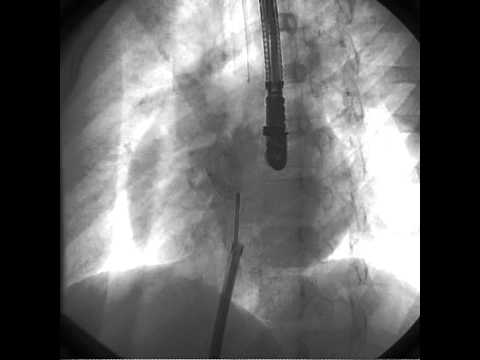

Transcatheter Closure - Movie 6: Pull and push on fluoro

Transcatheter Closure - Movie 8: Detachment on fluoro